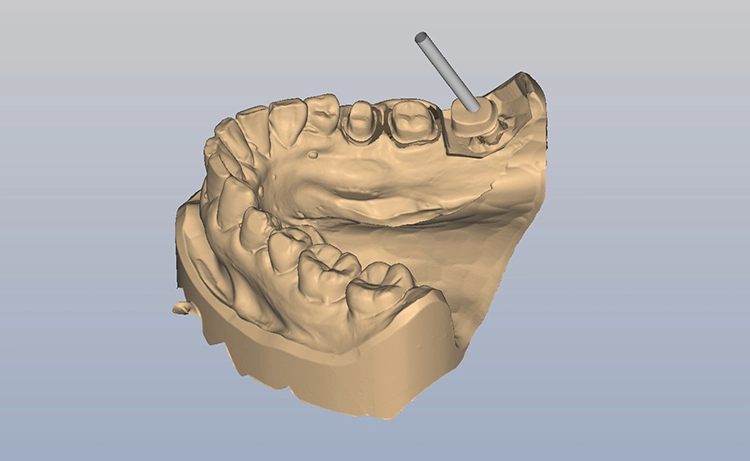

Bilder: Dr. Lampson / HannkerNach dem Ausgießen der Abformung sowie dem Scan des Gips- und Antagonistenmodells (Abb. 11a bis d) folgten das Kronendesign und die Fräsparametereinstellung per CAD/CAM-Programm (PowerMill Pro, Autodesk) (Abb. 12). Hergestellt wurden die Kronen aus Lithium-Disilikat-CAD/CAM-Blöcken (InitialTM LiSi Block, Farbe A2) (Abb. 13), die sich insbesondere durch eine hohe Opaleszenz bei hochtransluzenten (HT) Farbtönen auszeichnen und so auch ohne weitere Charakterisierung hochästhetische Ergebnisse erzielen.

Bilder: Dr. Lampson / HannkerNach 35-minütigem Schleifen (Exocad PowerMill CAM, DMG) wurde die Restauration aus dem Block entfernt und der Bereich der Anstiftung geglättet. Anschließend galt es, die Kronen auf den jeweiligen Formen und am Modell zu prüfen, wobei sich bereits eine perfekte Randpassung zeigte (Abb. 14 und 15). Danach erfolgte die Glaslötung der Implantatkrone auf das individuell angepasste Zirkonoxid-Abutment (Abb. 16).